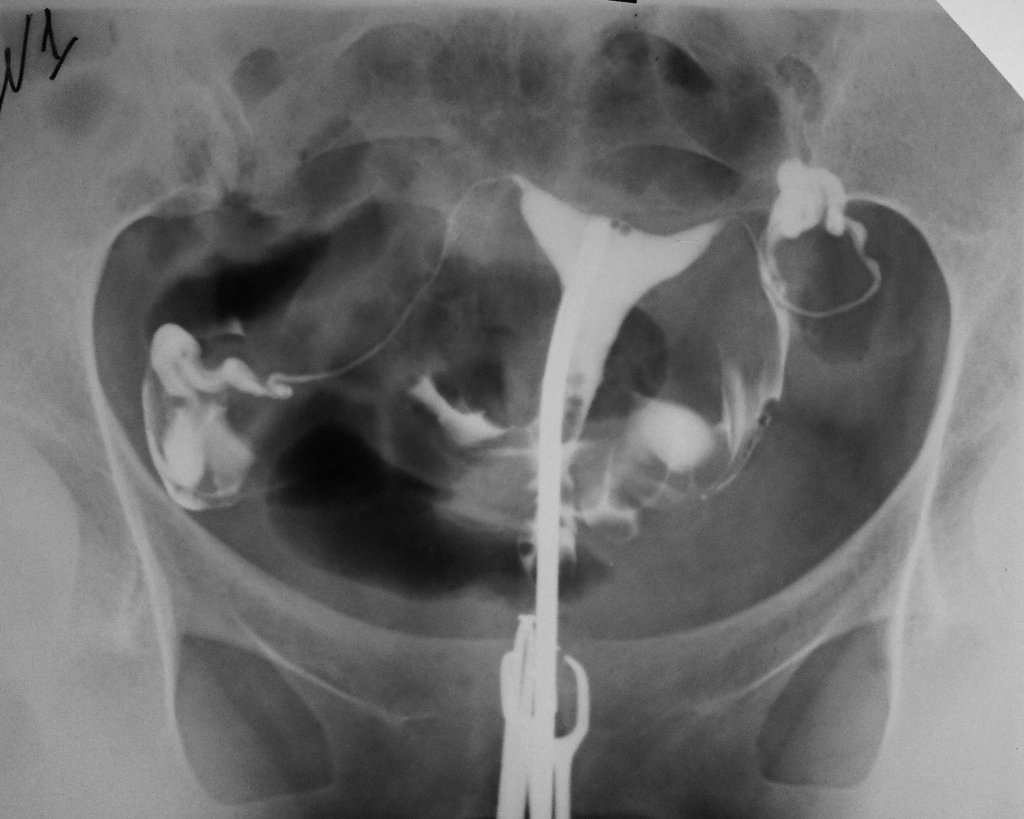

Рентген матки и яичников

Гистеросальпингография — это рентгеновское исследование матки и её придатков с помощью введения в полость контрастного препарата. Оно проводится также после окончания менструации (обычно на 7-й день). С помощью такого метода можно увидеть, что контраст проходит за пределами матки, а её полость увеличена.

По уровню расположения контрастного препарата можно выявить наличие спаек

При гистеросальпингографии существует вероятность развития аллергической реакции на химический препарат, вводимый в полость матки. Одна из моих знакомых, проходившая это исследование в клинике при подозрении на аденомиоз, столкнулась с такой проблемой. В ответ на введение средства у женщины развился отёк Квинке: покраснело и раздулось лицо, стало трудно дышать. Врачи экстренно произвели укол Адреналина, после чего состояние больной стабилизировалось. Выяснилось, что женщина не знала о наличии у себя аллергии. Чтобы избежать подобных осложнений, рекомендуется перед началом процедуры пройти тест на чувствительность к препарату.